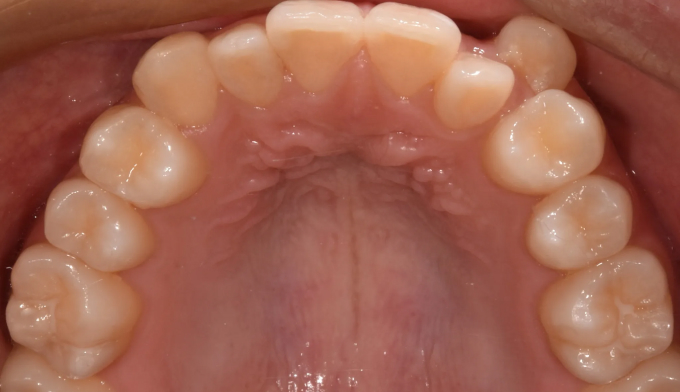

덧니

얇은 입술과 뒤로 들어간 입술을 가지고 있기 때문에 발치를 하지 않고 확장과 후방이동을 통해 최대한 공간을 마련하여 교정하기로 하였습니다.

덧니뿐만 아니라 앞니의 교합이 좋지 않아 윗니가 아랫니를 덮지 못하는 개방교합도 동시에 나타납니다.

총 교정기간은 21개월입니다.

원래 앞니의 길이가 위아래로 긴 형태를 가지고 있어서 치아의 길이를 조금 더 줄이면 보다 더 심미적이고 조화로운 형태를 나타냈을텐데, 환자가 치아의 형태를 바꾸길 원하지 않아 조금은 아쉬운 결과를 보입니다.